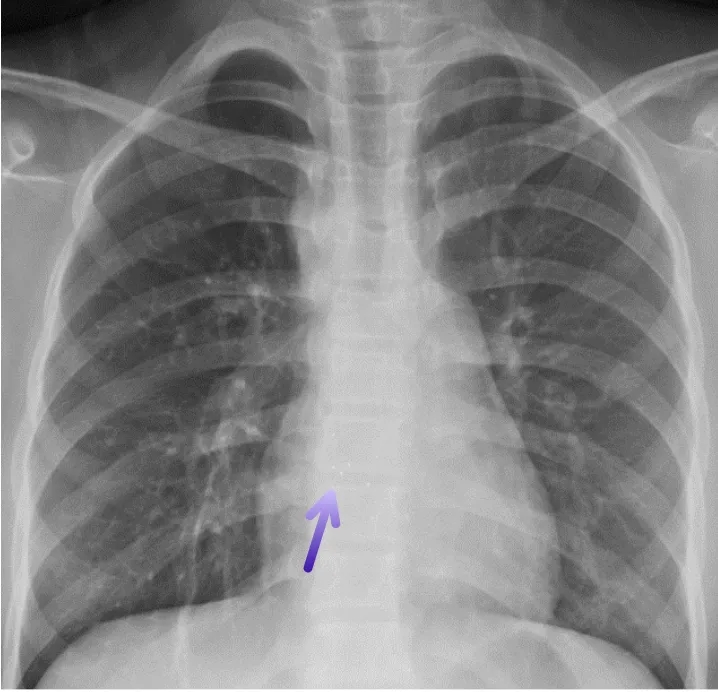

术后复查胸片

术后复查心电图,无房室传导阻滞